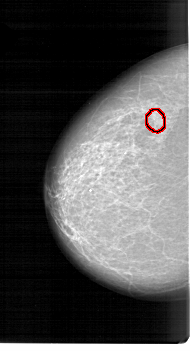

A_1261_1.LEFT_MLO

LEFT_MLO LINES 6526 PIXELS_PER_LINE 3706 BITS_PER_PIXEL 12 RESOLUTION 43.5 OVERLAY

FILE: A_1261_1.LEFT_MLO.OVERLAY

TOTAL_ABNORMALITIES 1

ABNORMALITY 1

LESION_TYPE CALCIFICATION TYPE PLEOMORPHIC DISTRIBUTION CLUSTERED

ASSESSMENT 4

SUBTLETY 4

PATHOLOGY MALIGNANT

TOTAL_OUTLINES 1

BOUNDARY